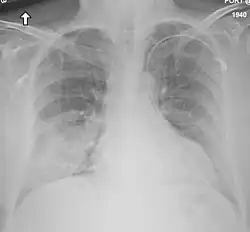

Medical imaging

Chest X-ray findings tend to show bilateral patchy infiltrates consistent with viral pneumonitis and acute respiratory distress syndrome (ARDS). Lower lobes tend to be more involved. CT scans show interstitial infiltrates.[29]